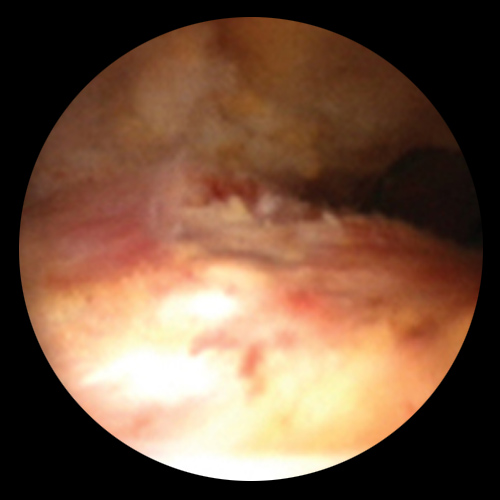

관절내시경은 작은 절개를 통해 초소형 카메라와 특수 기구를 관절 내부에 삽입하여 손상 부위를 직접 확인하고 치료하는 방법입니다.

어깨, 무릎, 발목 등 다양한 관절에 적용되며, 진단과 치료를 동시에 시행할 수 있는 최소침습 수술입니다.

다만, 회전근개 손상이 동반되었고 그 손상이 만성적인 경우,

운동 재활 후에도 증상 호전이 없다면 수술적 치료를 고려할 수 있습니다.

차병원은 손상된 조직 부위를 정리하고, 만약 파열된 부분이 있다면 이를 봉합해주는 시술을 시행합니다.